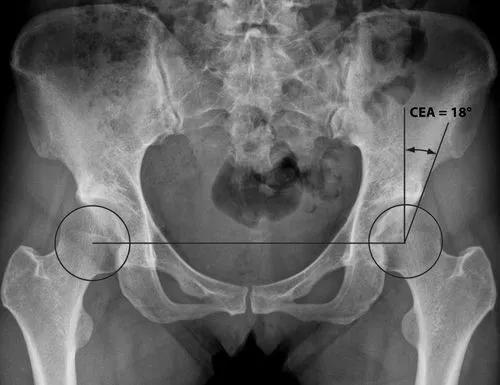

1、髋关节的X线片

在髋关节正位上,髋白发育不良主要表现为髋白发育浅小或浅平,股骨头的负重侧间隙增宽,并继发或不继发骨性关节炎。髋关节正位、蛙位X线片是了解与判断髋关节发育不良程度的最基础的影像学检查。

正常髋关节 髋关节发育不良